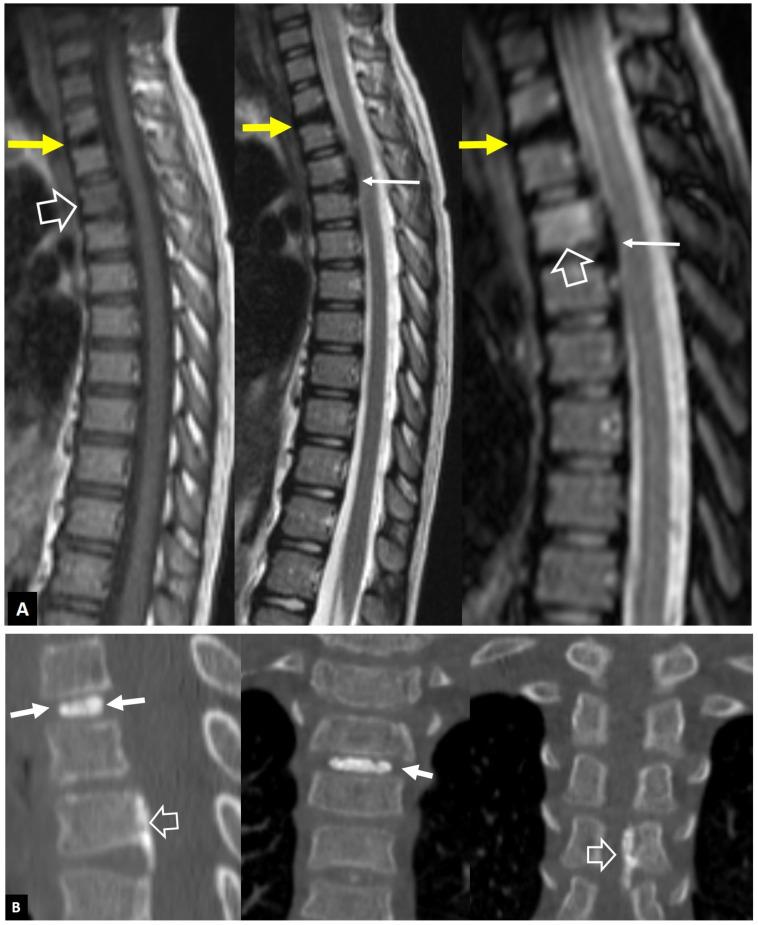

A series of conditions can mimic musculoskeletal infections on imaging, complicating their diagnosis and affecting the treatment. Depending on the anatomical location, different conditions can manifest with clinical and imaging findings that mimic infections. Herein we present a wide spectrum of the musculoskeletal disorders of the axial skeleton, long bones, peripheral joints, and soft tissue that may manifest as infectious processes, and we focus on the potential mimics of osteomyelitis, septic arthritis, and infectious spondylodiscitis that are common in clinical practice. We present the typical imaging characteristics of each musculoskeletal infection, followed by mimicking conditions.

一系列病症在影像学上可模拟肌肉骨骼感染,使诊断复杂化并影响治疗。根据解剖位置的不同,不同病症可表现出类似感染的临床和影像学表现。在此,我们展示了轴向骨骼、长骨、外周关节和软组织的广泛肌肉骨骼疾病,这些疾病可能表现为感染过程,并且我们重点关注临床实践中常见的骨髓炎、化脓性关节炎和感染性脊椎间盘炎的潜在模仿病症。我们介绍了每种肌肉骨骼感染的典型影像学特征,随后是模仿病症。